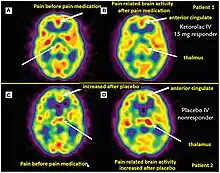

Advancements in MRI technology have expanded its capabilities in theranostics. Techniques such as functional MRI (fMRI) enable the assessment of brain activation and connectivity, while diffusion-weighted imaging (DWI) provides insights into tissue microstructure. The development of molecular imaging agents, such as superparamagnetic iron oxide nanoparticles, allows for targeted imaging and tracking of specific molecular entities.[11]